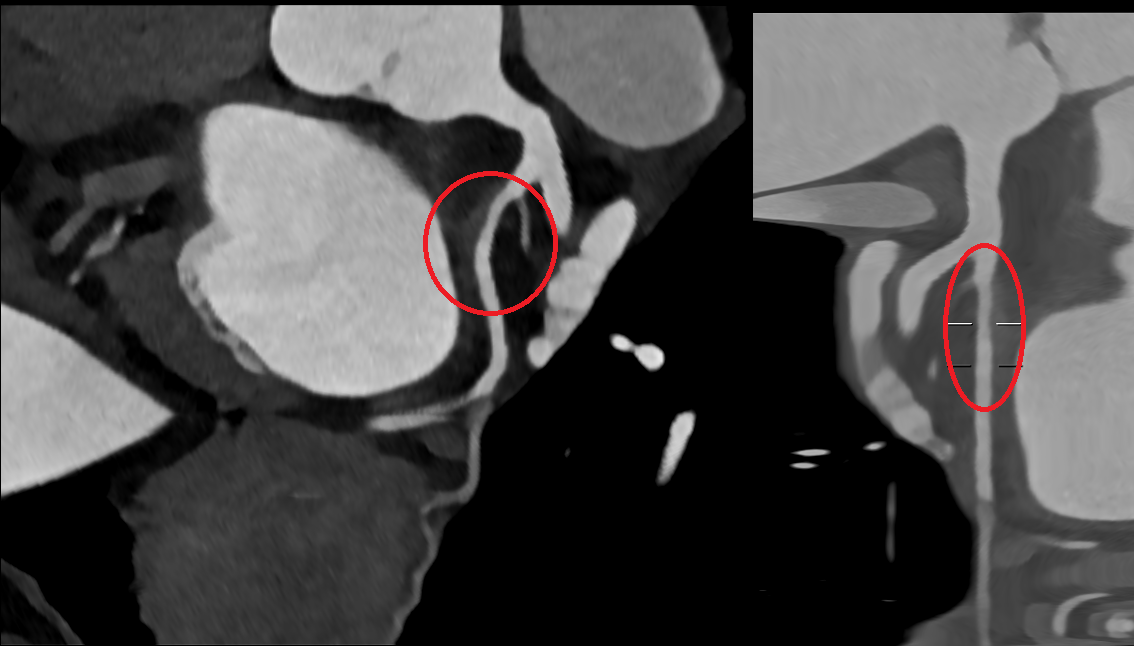

We report the case of a 61-year-old woman presenting with chest pain radiating to the left arm. EKG showed inferolateral repolarization abnormalities. Laboratory revealed mild elevation in troponin (0.76). Transthoracic echocardiography demonstrated mildly reduced systolic function with posterolateral wall akinesia (ejection fraction 48%). The patient was referred for coronary angiography showing no significant stenoses; however, a focal narrowing of the proximal circumflex artery (LCX) was observed, consistent with type 3 spontaneous coronary artery dissection (SCAD) according to the Yip–Saw classification (Fig. 1). Given the risk of iatrogenic propagation of the dissection and recommendations to minimize coronary instrumentation in SCAD, intracoronary imaging was avoided, and we performed instead coronary computed tomography angiography (CCTA) demonstrating mild stenosis of the LCX with mural hyperdensity, consistent with an intramural hematoma (Fig. 2). On day four, the patient experienced angina similar to the initial episode, with ECG changes and an increase in troponin (1.2). Repeat coronary angiography demonstrated progression of the dissection from the LCX to the distal segment of the first obtuse marginal branch, corresponding to evolution toward type IIb SCAD (Fig. 3). Given the limited myocardial territory at risk and the absence of ongoing symptoms, conservative management was continued. Patient was discharged on day ten on a beta-blocker and aspirin.with a planned follow-up CCTA at six months. This case highlights that in SCAD, particularly type 3 and proximal lesions, a conservative approach is often the safest strategy, with non-invasive imaging playing a key role in diagnosis, follow-up, and therapeutic guidance.